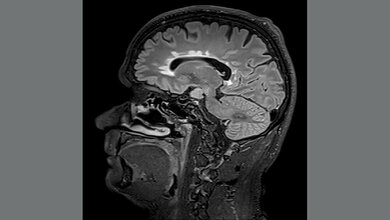

Mit mehr als 280.000 Betroffenen in Deutschland und jährlich 15.000 neuen Diagnosen ist Multiple Sklerose (MS) die häufigste entzündliche Erkrankung des zentralen Nervensystems. Durch den Angriff des eigenen Immunsystems auf die isolierende Schicht der Nervenfasern kann es zu einer Reihe an unterschiedlichen Symptomen kommen – darunter Sehstörungen, Lähmungen oder Missempfindungen. Die genaue Ursache für die Erkrankung kennt man nicht, sie ist eine multifaktorielle Erkrankung. Verschiedene Umweltfaktoren spielen dabei genauso eine Rolle wie die Genetik. Vor allem Mikroorganismen des Darms stehen seit längerem unter Verdacht, einer der Auslöser zu sein.